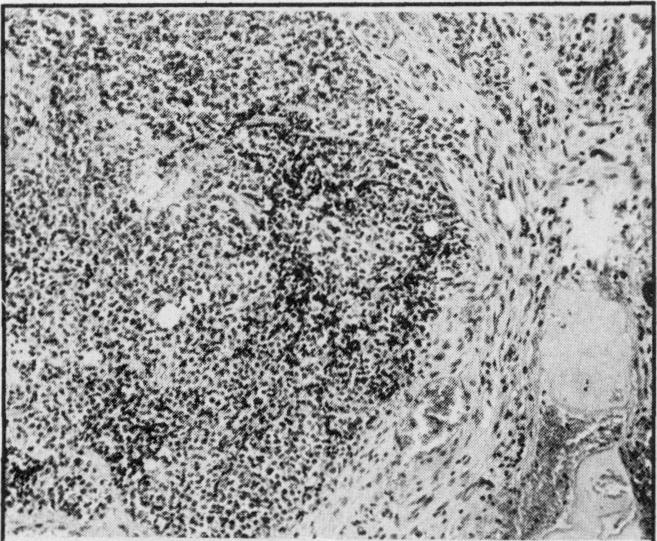

Although metastases to bones from solid tumors are very common, involvement of small bones of the hands and feet is extremely rare. One half of the cases reported in literature resulted from a primary tumor in the lung. Four cases seen over the last four years with metastases to bones of the hand and one case with metastases to foot bones are discussed. None of these patients had a lung primary tumor. Three of the four patients who had metastases to hand bones had the disease on the right side.

尽管实体瘤骨转移很常见,但手足小骨受累极为罕见。文献报道的病例中有一半源于原发性肺癌。本文讨论了过去四年中见到的4例手部骨转移病例和1例足部骨转移病例。这些患者均无原发性肺癌。4例手部骨转移患者中有3例病变位于右侧。